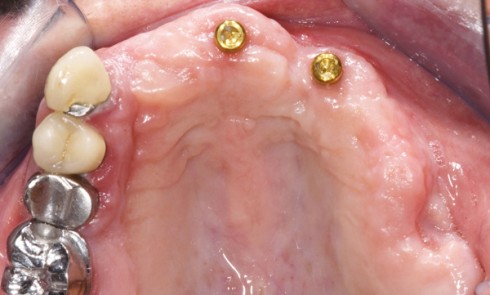

Une patiente consulte car elle ne supporte plus le port de sa prothèse amovible mandibulaire, pourtant suffisamment stable grâce à...